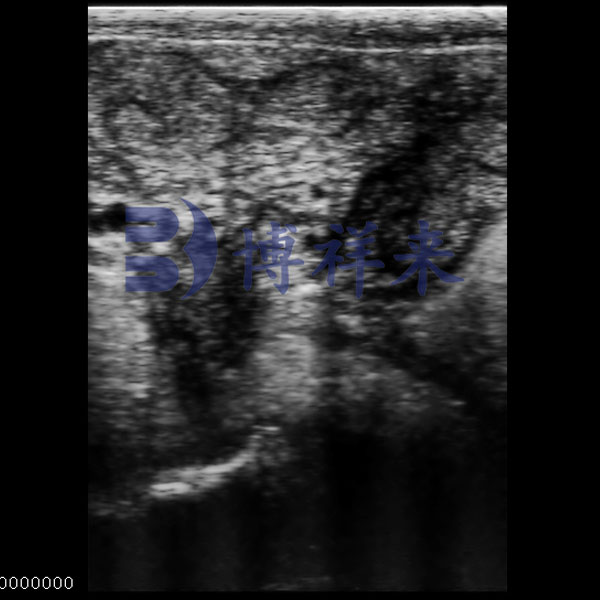

Bovine Uterus Ultrasound

● Shows complete uterine section with clear internal zoning.

● Balanced contrast for identifying tissue makeup.

● Displays wall thickness and lumen features.

● Suitable for reproductive assessment.